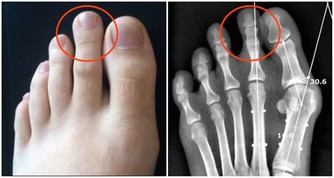

看看有沒有「黃色瘤」。

中老年人,尤其是女性,眼瞼上新出現黃色、橘色或者棕紅色斑塊或者結節,不痛不癢,就很可能是黃色瘤。

這瘤經常長在上眼瞼的內眼角處,也可能出現在臉部其他部位或膝蓋上,針頭或黃豆大小,邊緣略高出皮膚表面,質地較柔軟。